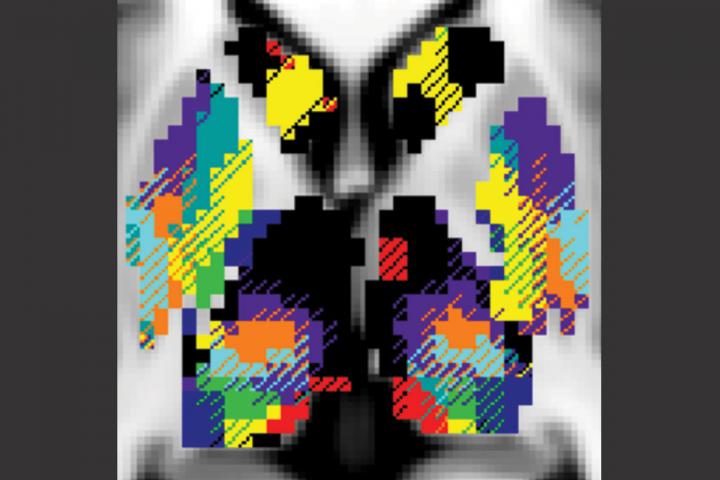

image: Brain networks corresponding to functions such as vision (blue) and attention (green) mingle and share information in structures deep inside the brain, as seen, for example, in the bottom right corner of this color-coded composite MRI image. Researchers at Washington University School of Medicine in St. Louis have mapped nine functional networks in the deep-brain structures of 10 healthy people, an accomplishment that could lead to improvements in deep-brain stimulation therapy for severe cases of Parkinson's disease and other neurological conditions.

Using data from a group of Washington University scientists who scanned themselves at night as part of the so-called Midnight Scan Club, the researchers analyzed 10 hours of MRI brain scan data on each of 10 individuals. From this, they created 3D maps color-coded by functional network for each individual. One of the functional networks is devoted to vision, two relate to movement, two involve paying attention, three relate to goal-directed behaviors, and the last network is the default network, which is active when the brain is at rest.